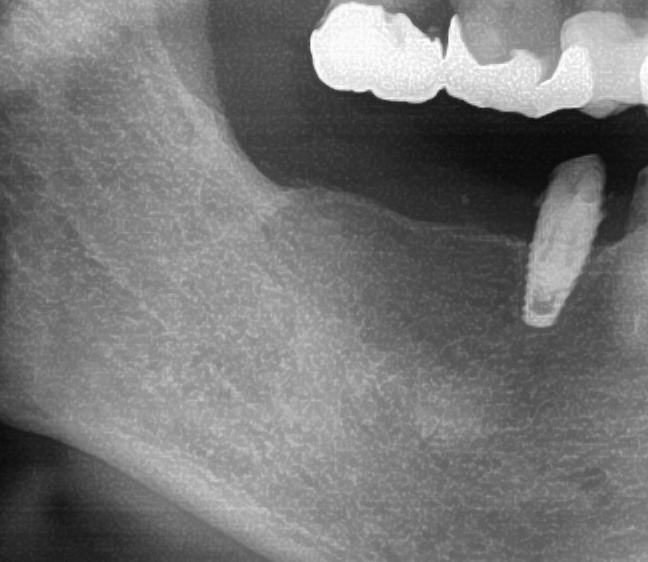

今回の患者様はインプラント植立を希望され、右下6番目・7番目の2本の植立が決まりました。

しっかりとインプラント埋め込まれた後は、動揺がないか、噛んだ時に当たらないかなどを確認して、最後にパノラマ写真を撮影して今回のオペは終了となりました。